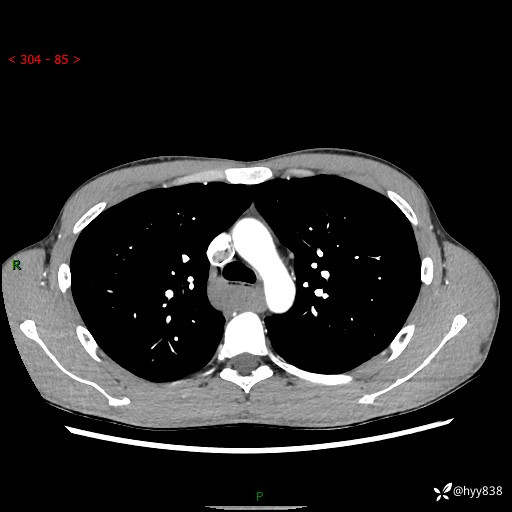

年轻男性,发现后纵隔占位1周余。征象简单,难在定位---结果公布~

现病史:患者于1周前体检行检查发现后纵隔占位,患者平素无明显咳嗽咳痰,无心慌、胸闷、胸痛、呼吸困难、低热、盗汗,无头痛、头晕,无腹痛、腹胀等不适。现患者欲求进一步治疗,遂来我院就诊,以“纵隔占位”收入我科。 患者自起病以来,精神可,睡眠可,饮食可,大小便正常,体重无明显改变。

胸部CT平扫+增强